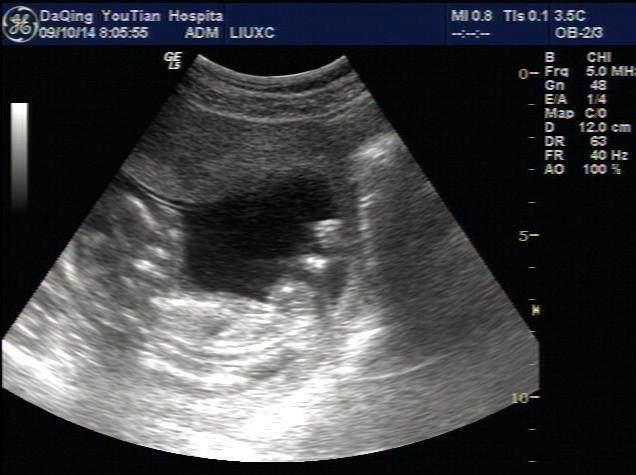

除了以上常用的方式,B超也是我们常遇到的一种检查方式,尤其对于女性而言,那B超有没有辐射呢?

B超超声检查是利用声波反射,得到不同的回声来形成影像,跟朝水里扔石头听回声来测深度差不多一个道理。

超声检查是利用声波反射成像,没有辐射!

B超主要筛查腹腔、盆腔内器官是不是有病变,包括:乳腺、甲状腺、肝脏、肾脏、胰腺、胆囊、脾脏、膀胱、子宫、卵巢等。心脏部位的检查也常会用到B超。